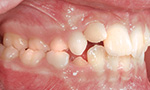

Die häufigsten Fehlstellungen

Nach Prüfung der Funktionen des Gebisses, wie zum Beispiel des Ineinanderpassens der Zahnreihen oder der Funktion des Kiefergelenks, steht fest, welche der folgenden Fehlstellungen vorliegt:

Überzählige Zähne

Es sind von Natur aus zu viele Zähne angelegt, die sich gegenseitig am Durchbruch hindern.